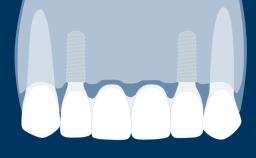

Fixed vs. Removable Prosthodontics for Restoring the Edentulous Maxilla

Fixed and removable prosthodontic implant therapy for restoration of the edentulous maxilla is both complex and challenging. Careful assessment and planning is needed in each individual case to explore whether a fixed or a removable solution will be the more suitable to satisfy the patient’s preference for optimal esthetics, phonetics, comfort and function. This Learning Pathway explores the prosthodontically driven treatment planning based on structured assessment, considered diagnosis and practical application in clinical case examples.